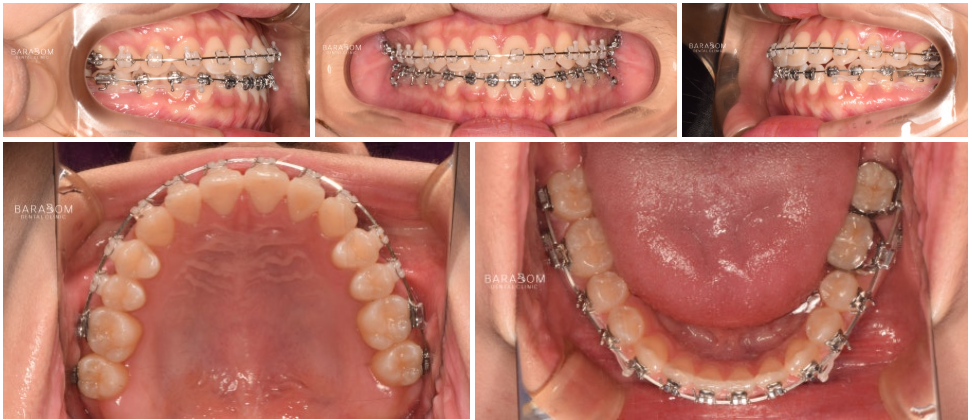

안모의 문제뿐만 아니라

부정교합도 함께 관찰됩니다.

안모와 동일하게 좌우

다른 문제를 가지고 있죠.

1️⃣좌측은 일부 치아가

거꾸로 물리는 반대교합 양상이

확인됩니다.

이런 경우 불안정한 힘이

치아에 가해져 파절로

이어질 수 있습니다.

2️⃣우측은 앞니의 끝부분 즉 절단연끼리

맞물리고 있는데요,

이를 절단 교합이라 부릅니다.

이렇게 맞물리는 양상 역시

힘을 고르게 분산시키기 어려워

절단연 파절로 이어질 수 있으며

턱관절에 안정을 찾기 어렵고

과도한 긴장 상태를 유지하게 됩니다.

윗니가 아랫니를 덮는 것이

정상적인데, 이 경우

정반대로 아래가 위를 덮는 듯한

모습이 관찰됩니다.

✅더불어 구치부의 맞물림 역시

올바르지 못한데요,

윗턱 성장 부전이 있어

골격성 3급으로 진단됩니다.

더불어 아랫턱이 좌측으로 변위되며

비대칭을 이루고 있습니다.

또한 작은 위턱으로 인해

위 앞니의 위치 자체가

아래 앞니 보다 뒤에 위치하게 되는데,

이를 보상하기 위해 앞니들이

순측경사(앞으로 뻐드러짐)되어 있습니다.

👀웃었을 때 치아와 잇몸이

거의 드러나지 않아

부자연스럽다는 느낌이 들며,

좌우가 달라 어색한 느낌이

강하게 들고 있습니다.